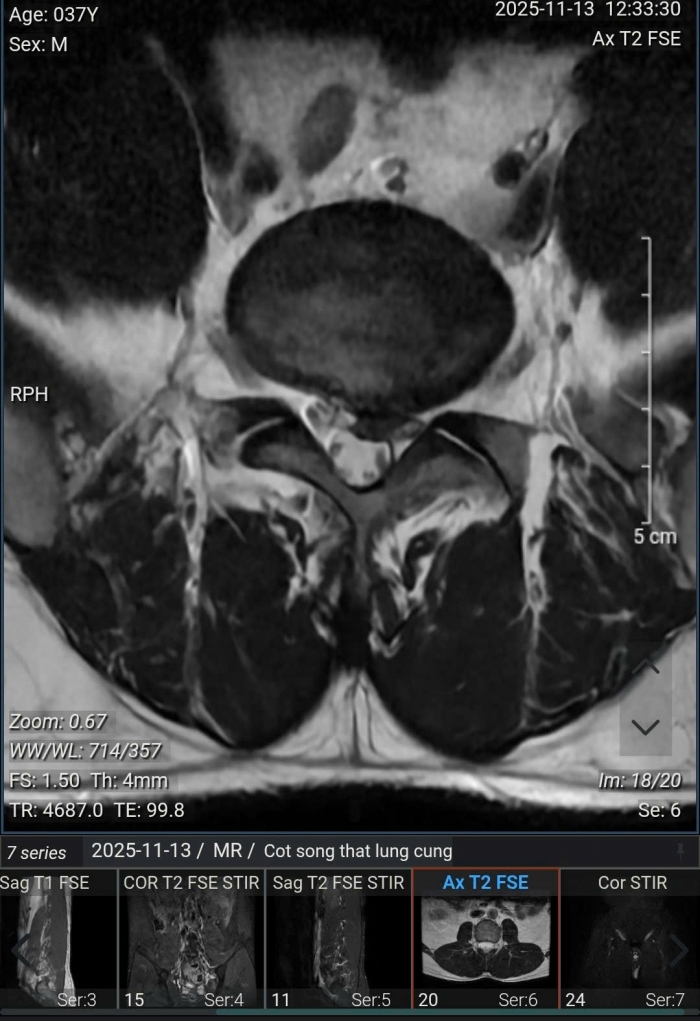

Kết quả chụp MRI cho thấy, bệnh nhân bị thoái hóa cột sống thắt lưng, thoát vị nội xốp các đĩa đệm từ L2/3 đến L5/S1, phình - thoát vị đĩa đệm L4/5 ra sau thể trung tâm gây chèn ép bao màng cứng, gây hẹp nhẹ ống sống, không gây chèn ép rõ rệt các rễ thần kinh; phình - thoát vị đĩa đệm L5/S1 ra sau thể trung tâm lệch trái gây chèn ép bao màng cứng, gây hẹp ống sống, hẹp ngách bên - lỗ tiếp và chèn ép các rễ thần kinh 1 bên ngang mức (trái > phải).

Ảnh chụp MRI của bệnh nhân nam 37 tuổi tại Hà Nội.